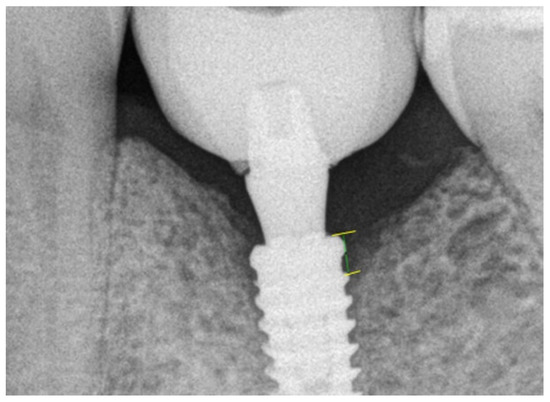

2.3. Radiographic Evaluation